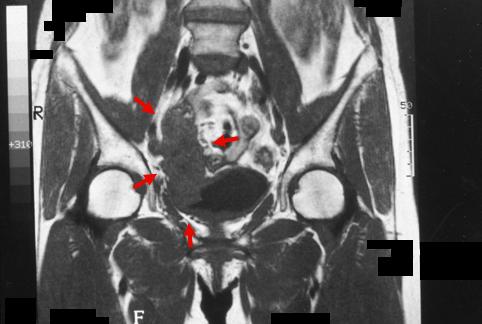

Advanced cancer of the appendix with invasion to the urinary bladder.

Malignant epithelial tumor/Adenocarcinoma

Large intestine(Colon)/Appendix

MRI

Type 2 Ulcerated type with clear margin/

25 - 29

serosa (adventitia)